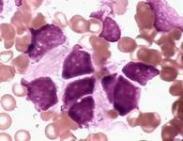

小兒神經(jīng)母細(xì)胞瘤

• 小兒神經(jīng)母細(xì)胞瘤

628健康網(wǎng)為您分享有關(guān)小兒神經(jīng)母細(xì)胞瘤的癥狀,小兒神經(jīng)母細(xì)胞瘤的治療方法,小兒神經(jīng)母細(xì)胞瘤的預(yù)防知識(shí),小兒神經(jīng)母細(xì)胞...